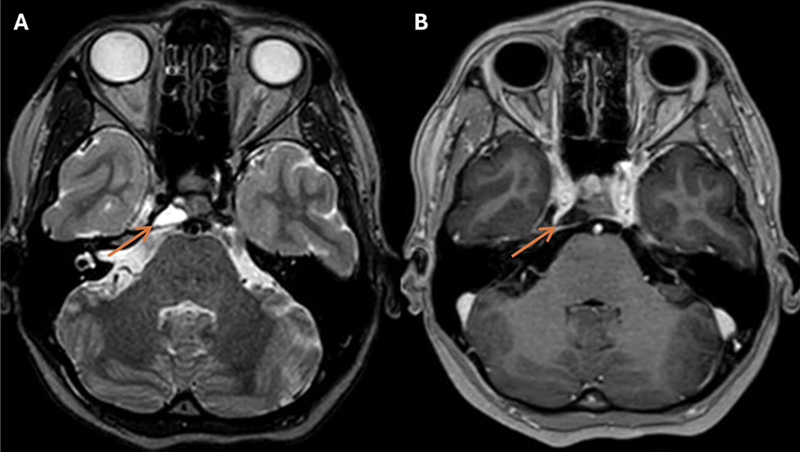

Case description: A 23-year-old woman presented with right abducens nerve palsy. Computed tomography and magnetic resonance imaging (MRI) revealed an off-midline petroclival lesion compressing the abducens nerve with characteristics of a chondrosarcoma. Preoperative MRI indicated spontaneous lesion regression, and the abducens nerve showed clinical improvement. Hence, the planned surgery was canceled. During the wait-and-scan period, abducens nerve palsy recurred. MRI confirmed lesion growth and showed an intratumoral linear structure indicative of blood. Even though preoperative MRI again demonstrated shrinkage, the lesion was surgically removed. Despite the unusual presentation, histopathological examination diagnosed a conventional chordoma. A second surgery was required to remove the residual tumor, after which the patient received high-dose photon beam therapy.